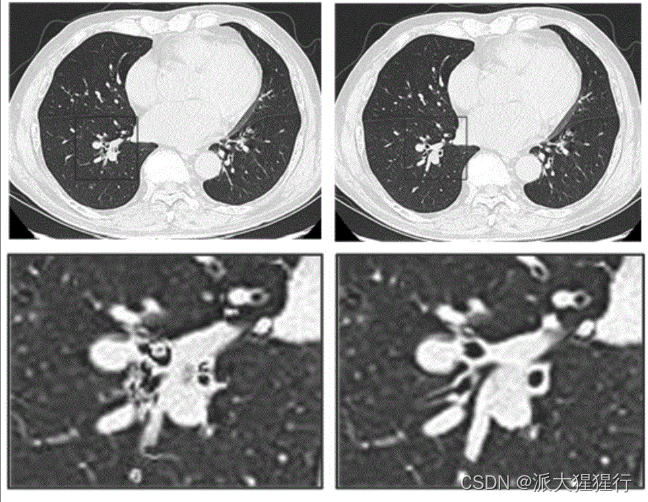

3.医学影像:医学图像处理中,包括X射线、超声波、磁共振等各种图像,对于诊断起着重要作用。超分辨率技术可以改善图像质量和精度,用于染色体分析、血球分类、X射线鉴别等应用,帮助医生做出更准确的诊断和治疗决策。

我们以五张图片为测试集,分别使用缩小再使用双三次插值得到模糊效果,再使用SRCNN进行超分。得出结果如下:

根据直觉观感以及评价指标,使用SRCNN进行超分辨率重建后的图像尽管重建图像没有完全复原原图,但在视觉上已经相当程度上恢复了图像的细节和提高了观感。而在PSNR和SSIM上相对于低分辨率图像均有显著的提高。这表明SRCNN在超分辨率任务上具有一定的重建能力,并能够改善图像的质量。